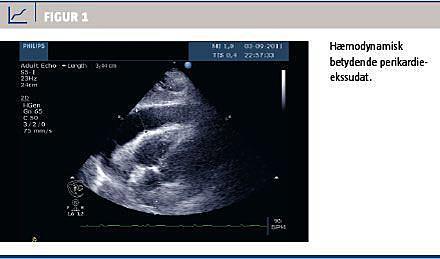

Syv uger senere blev patienten genindlagt med svær dyspnø, igen vigende EF og hæmodynamisk betydende perikardieekssudat (Figur 1), som udtømtes (i alt 900 ml). CRP-niveauet var på 190 mg/l. TnT-niveauet var normalt. Efter udskrivelsen blev patienten fulgt med ugentlige kontroller i den første måned, og man kunne konstatere nærnormalisering af EF.